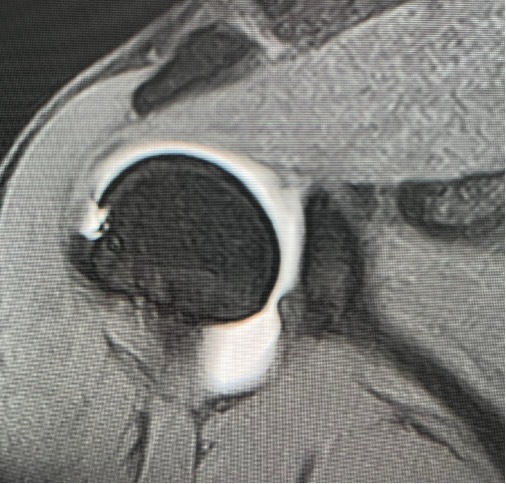

上方関節唇損傷(Superior Labrum Anterior and Posterior lesion、以下SLAP損傷)は野球やバレーボールなどのオーバーヘッドスポーツに多く起こる障害です。繰り返しの投球動作による反復動作により、上腕二頭筋関節唇複合体に負荷がかかり上方関節唇が関節窩から剥がれてしまう状態です。また投球動作の反復だけでなく、スライディング動作で腕を伸ばして手をついた際に受傷したりする場合もあります。自覚症状としては、投球動作時(レイトコッキング期に多い)の痛み、引っ掛かり感、不安定感などがあります。

投球動作におけるレイトコッキング期に肩が外転―外旋位に強制された際、上腕二頭筋腱に捻れが生じ、その付着部である上腕二頭筋関節唇複合体にも捻れ+牽引ストレスが加わり(Peel bach mechanisim)上方関節唇の剥離が生じます。

投球動作におけるレイトコッキング期に肩が外転―外旋位に強制された際、上腕二頭筋関節唇複合体が腱板(肩のインナーマッスル)に挟まれる状態(インターナルインピンジ)になり、関節唇の剥離が生じます。